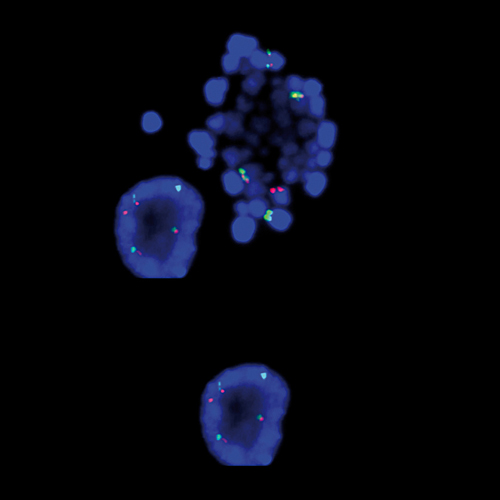

Hybridization of MYC TC break probe to a tissue section showing abarrant pattern (1GBR1G1BR).

Rearrangements of the proto oncogene MYC c-myc) have been consistently found in Burkitt's lymphoma tumor cells. In cases with the common t(8;14) chromosomal translocation, the MYC gene is translocated to chromosome 14 and rearranged with the immunoglobulin heavy chain genes; the breakpoint occurs 5' to the MYC gene and may disrupt the gene itself. In Burkitt's lymphoma showing the variant t(2;8) or t(8;22) translocations, the genes coding for the k and l immunoglobulin light chain are translocated to v-myc avian myelocytomatosis viral oncogene homolog (MYC or c-myc) chromosome 8. The MYC (8q24) Break probe is optimized to detect rearrangements involving the 8q24 locus in a triple-color, split assay on formalin fixed paraffin embedded tissue.